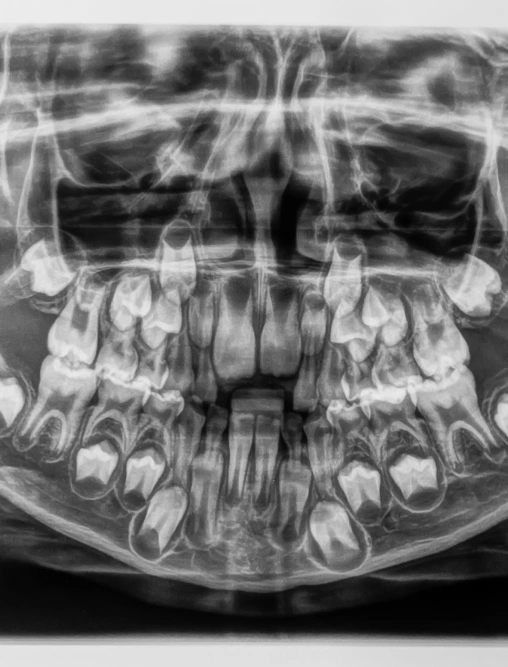

Panoramic X-rays provide a complete, 360-degree view of your teeth, jaw, and surrounding structures—all in one quick scan. While traditional X-rays focus on individual teeth, panoramic images give us a wide, detailed perspective of your oral health, including the jawbone, sinuses, and other key areas. This technology helps us detect issues such as bone loss, cavities, impacted teeth, and hidden abnormalities that may not appear during routine exams.

These images are especially valuable when planning advanced treatments like dental implants, extractions, and orthodontics. By using panoramic X-rays, we can evaluate your oral health more thoroughly, identify concerns early, and create the most accurate and effective treatment plan for your needs.